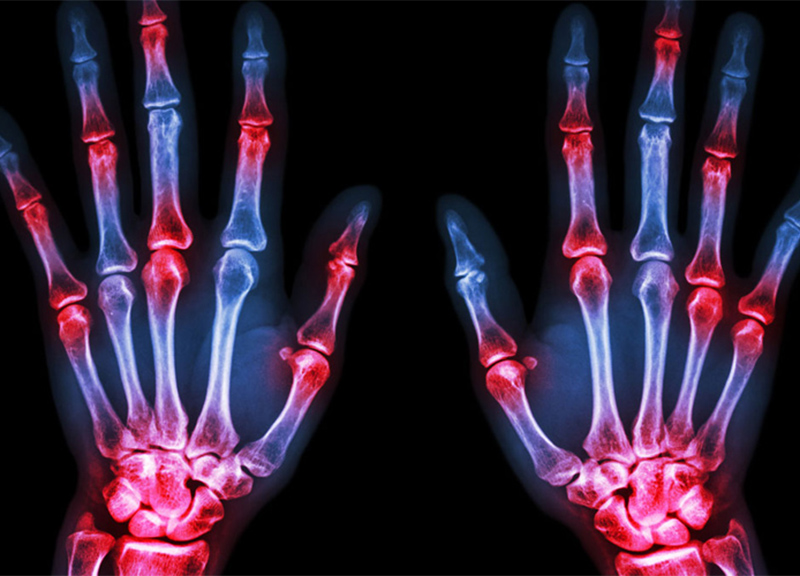

Sono circa 400mila gli italiani che soffrono di artrite reumatoide. Di questi quasi 55mila devono fare i conti anche con il diabete di tipo 2. Adesso c’è una speranza per chi al mattino presenta articolazioni gonfie e dolenti, o rigide che in molti casi finiscono addirittura per deformarsi. Un calvario, quello delle persone con artrite reumatoide, che purtroppo talvolta viene aggravato dal diabete di tipo 2: in Italia succede al 13,6 % dei pazienti, che per colpa della glicemia alta vedono peggiorare la qualità di vita e aumentare ulteriormente il rischio di conseguenze serie connesse all’AR, come infarti e ictus. Per loro potrebbe però essere di grande aiuto una terapia che in un sol colpo tiene a bada l’artrite reumatoide e fa scendere gli zuccheri nel sangue: lo dimostra uno studio italiano multicentrico appena pubblicato sulla rivista PLOS Medicine, coordinato dalla Cattedra di Reumatologia del Dipartimento di Biotecnologie e Scienze Cliniche Applicate dell’Università de L’Aquila, che è stato addirittura interrotto prima del previsto grazie agli ottimi risultati ottenuti nei pazienti trattati con un antagonista dell’interleuchina-1 (IL-1), una citochina infiammatoria. AR e diabete di tipo 2 condividerebbero infatti alcuni meccanismi molecolari e questo può essere sfruttato per semplificare il trattamento, scegliendo fra le diverse opzioni terapeutiche contro l’artrite reumatoide un farmaco che possa curare anche il diabete riuscendo a ridurre del 42% la quota dei pazienti con la glicemia fuori controllo.

“L’artrite reumatoide è una patologia infiammatoria cronica autoimmune che si associa spesso ad altre malattie come problemi cardiovascolari, infezioni, tumori, disturbi polmonari e neuropsichiatrici”, spiega Roberto Giacomelli, direttore della Divisione di Reumatologia del Dipartimento di Biotecnologie e Scienze Cliniche Applicate dell’Università de L’Aquila e coordinatore dello Studio. “Il diabete di tipo 2 è una delle patologie associate più frequenti: avere l’artrite reumatoide infatti raddoppia il rischio di ammalarsi di diabete. Le stime internazionali ipotizzano che la glicemia alta riguardi dal 15 al 50% dei pazienti con artrite reumatoide, secondo uno studio italiano recente condotto su 500 malati il problema in Italia riguarda il 13,6%. Considerando che nel nostro Paese vivono circa 400mila persone con artrite reumatoide, i pazienti che soffrono contemporaneamente di diabete di tipo 2 quindi sono poco meno di 55mila”.